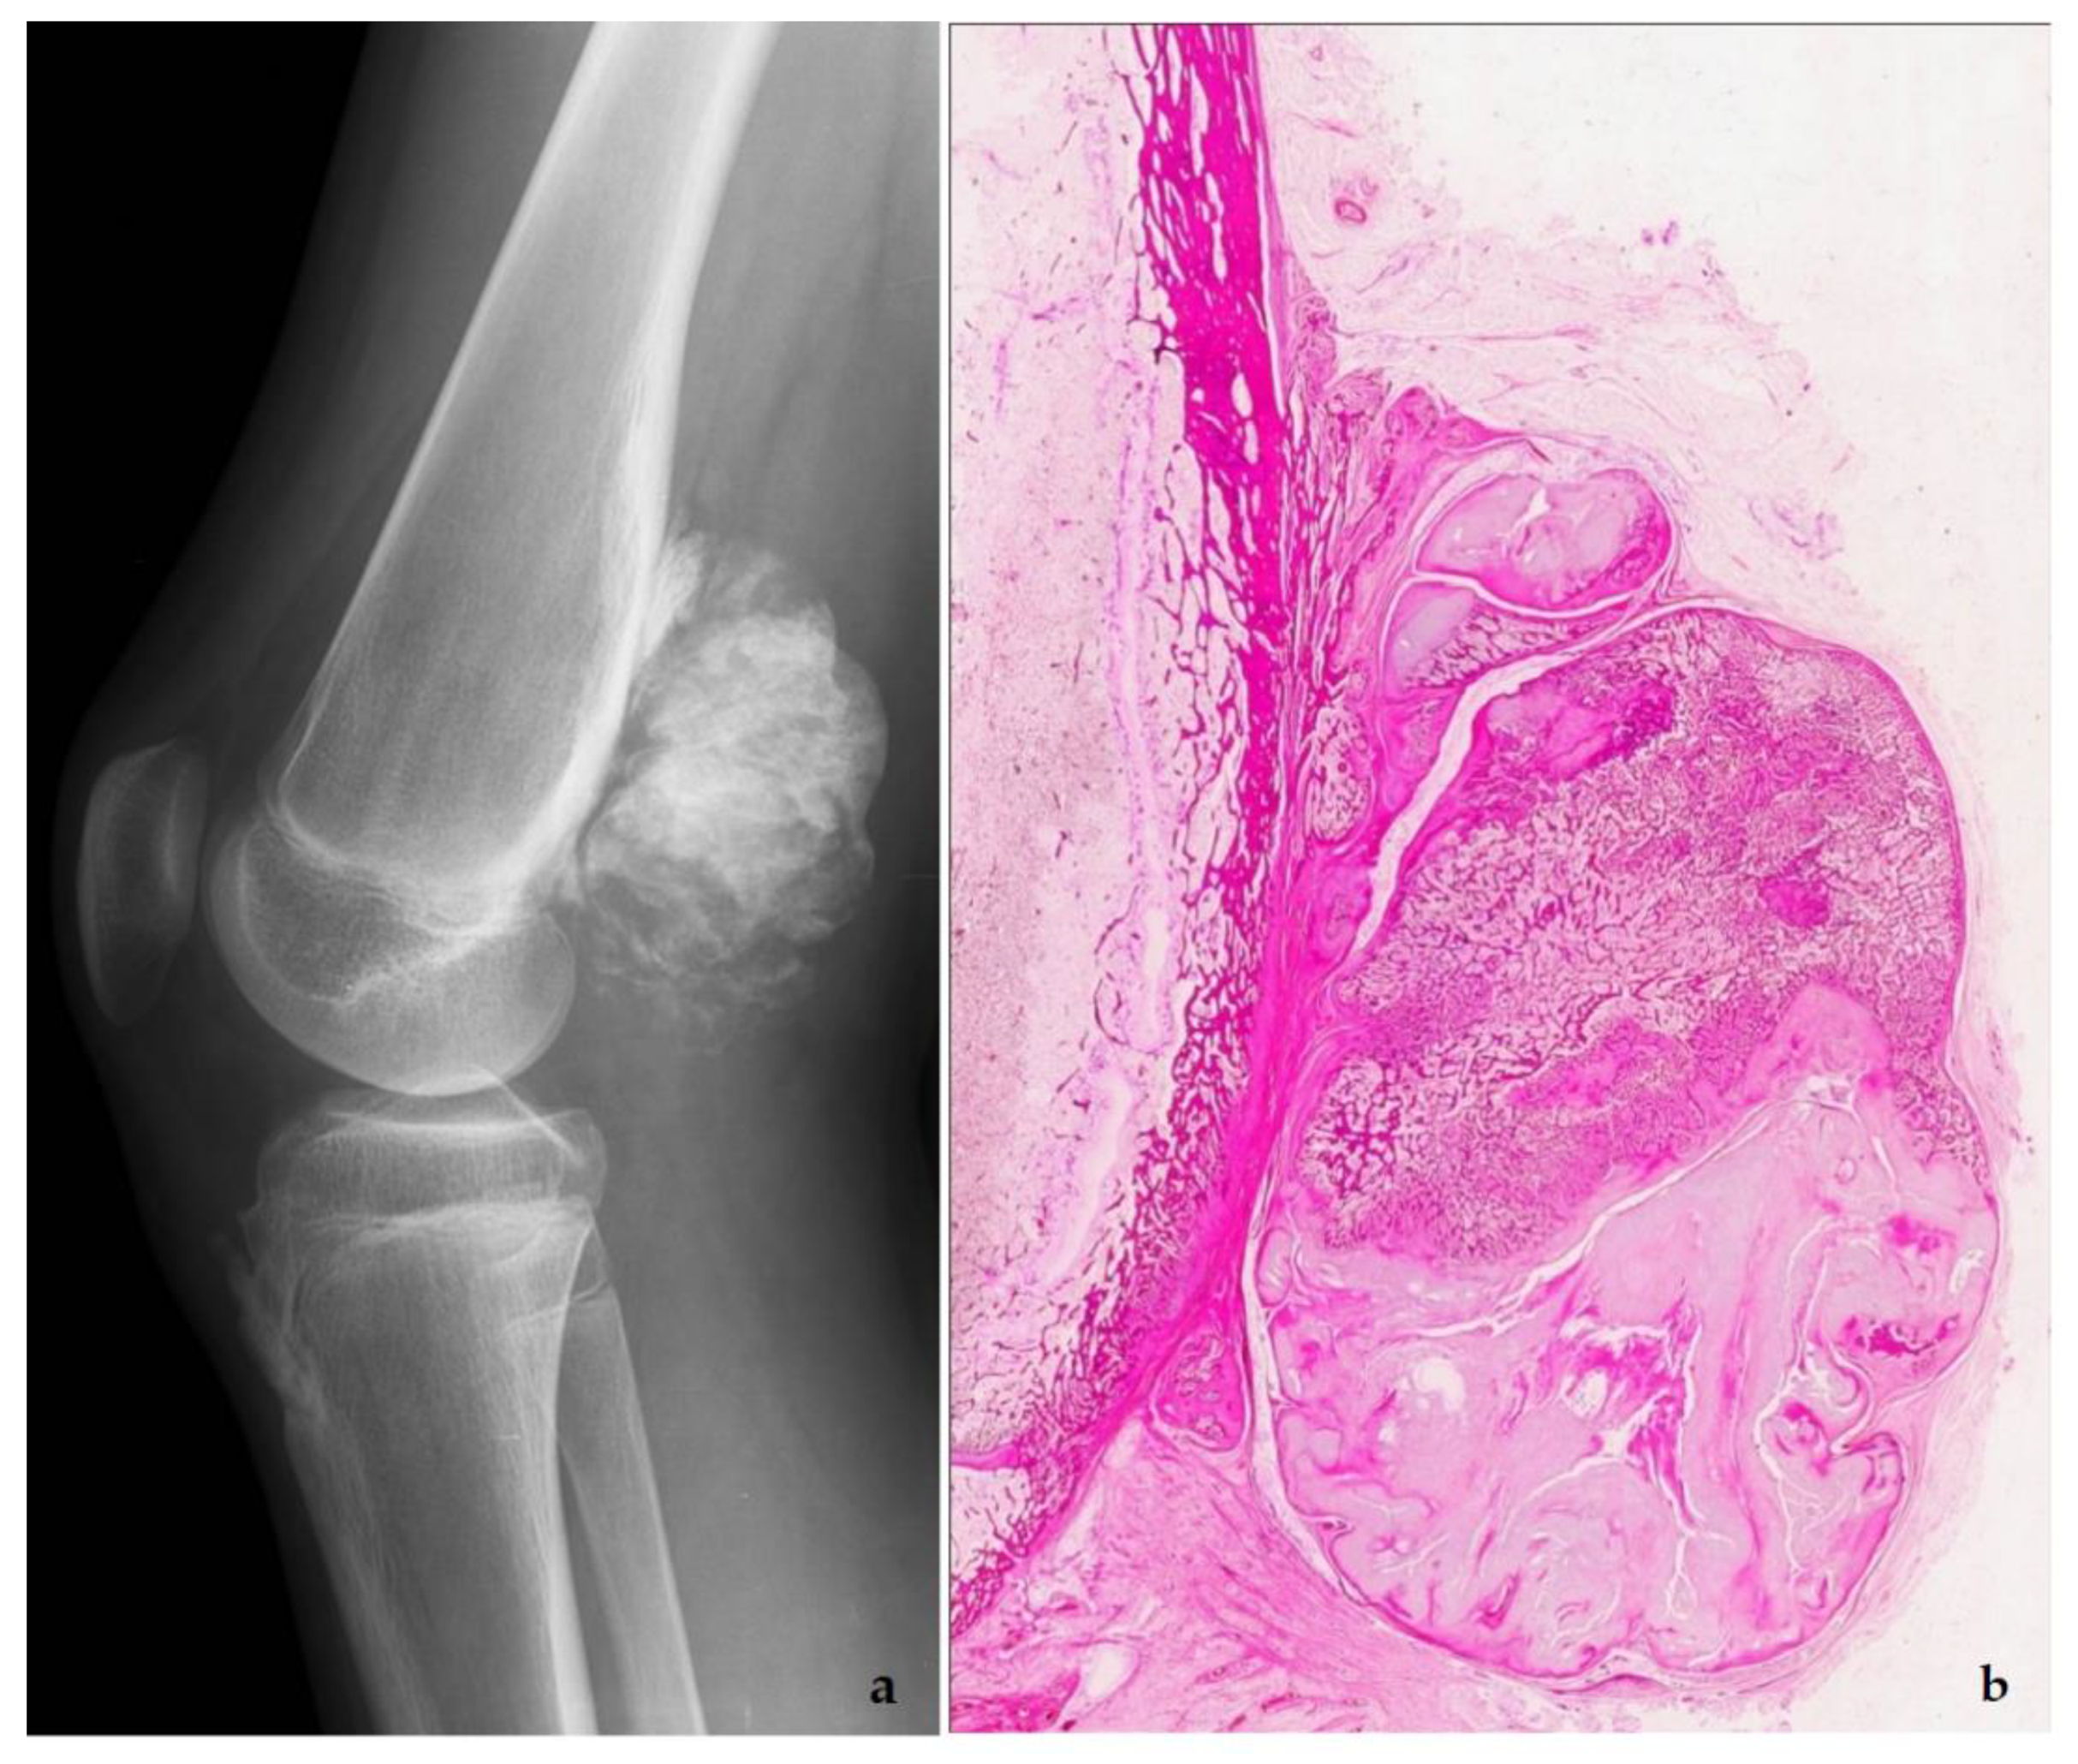

5. Low-Grade Osteosarcoma